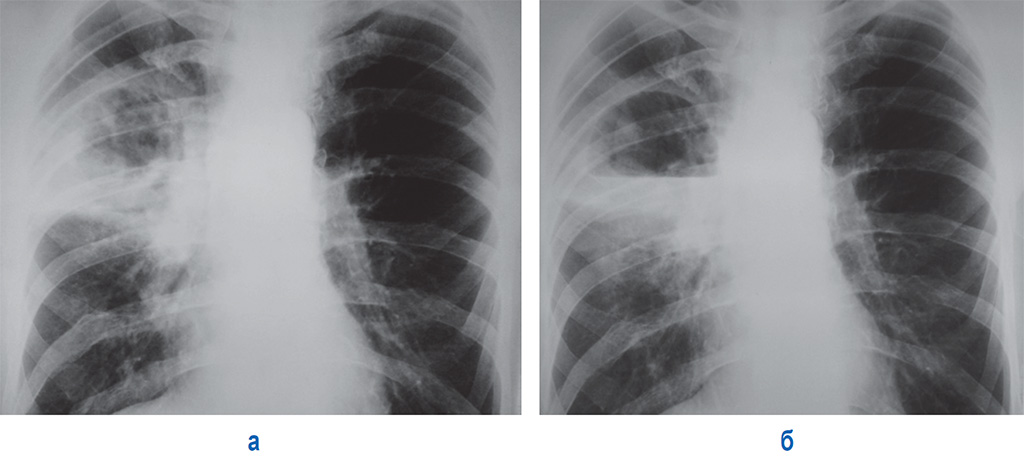

Бактериальная деструкция легких у детей презентация - 88 фото